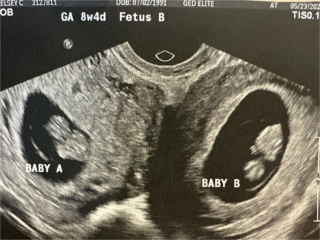

A americana Kelsey Hatcher, 32, tem uma condição rara: dois úteros ao invés de apenas um. Mas ao ficar grávida, ela teve uma experiência ainda mais incomum, com um feto crescendo em cada órgão reprodutor.

Isso só acontece com uma a cada um milhão de grávidas que possuem útero didelfo, nome técnico atribuído à malformação que gera duplicidade do órgão. A estimativa é de Richard Davis, especialista em medicina materno-fetal, que acompanha o caso de Kelsey.

Com a notícia, ela e o marido tentaram ficar otimistas com as necessidades para criar quatro filhos. Até que em maio, durante uma ultrassonografia periódica, receberam a notícia de que seriam cinco — são duas crianças do sexo feminino que se desenvolvem bem na barriga da mãe. Kelsey e o marido brincam que as meninas estão brigando quando as sentem chutar simultaneamente.